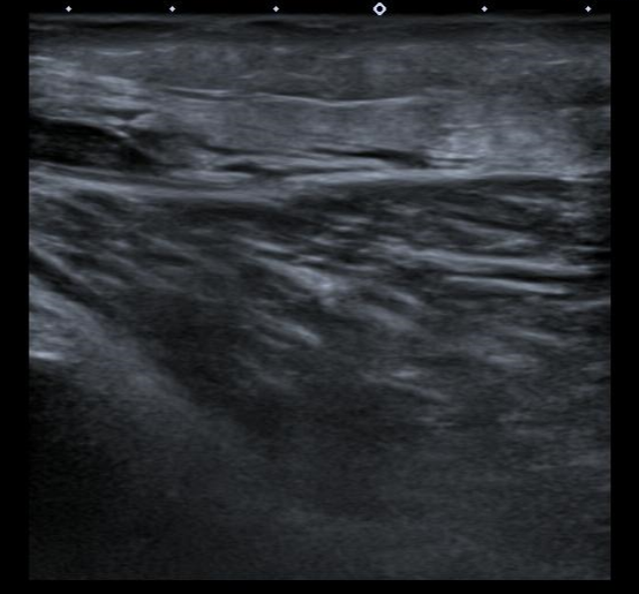

Ecografía Doppler miembros inferiores: venas permeable sin signos de TVP. En el hueco poplíteo de MID se observa una estructura anecoica de aproximadamente 17 x 14 mm (AP x T), con restos hiperecogénicos en su interior y cuyo polo inferior muestra una morfología irregular afilada, observándose láminas de líquido adyacentes. Hallazgos compatibles con rotura de quiste popliteo (de Baker).